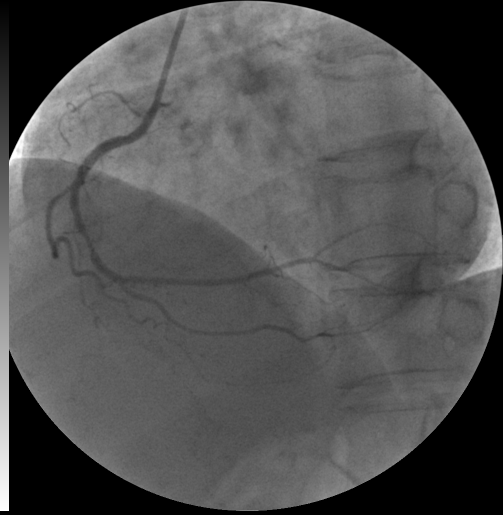

冠脉造影发现右冠状动脉中段狭窄百分之九十,随机给予支架置入治疗.

造影发现右冠状动脉闭塞

这是一名心绞痛的患者,活动后明显胸痛,造影发现右冠状动脉明显狭窄

肌钙蛋白轻微升高,急诊冠脉造影显示右冠状动脉近段99%狭窄(图3)

右侧冠状动脉中段严重狭窄一例

植入支架后,右冠状动脉血管完全开通.jpg